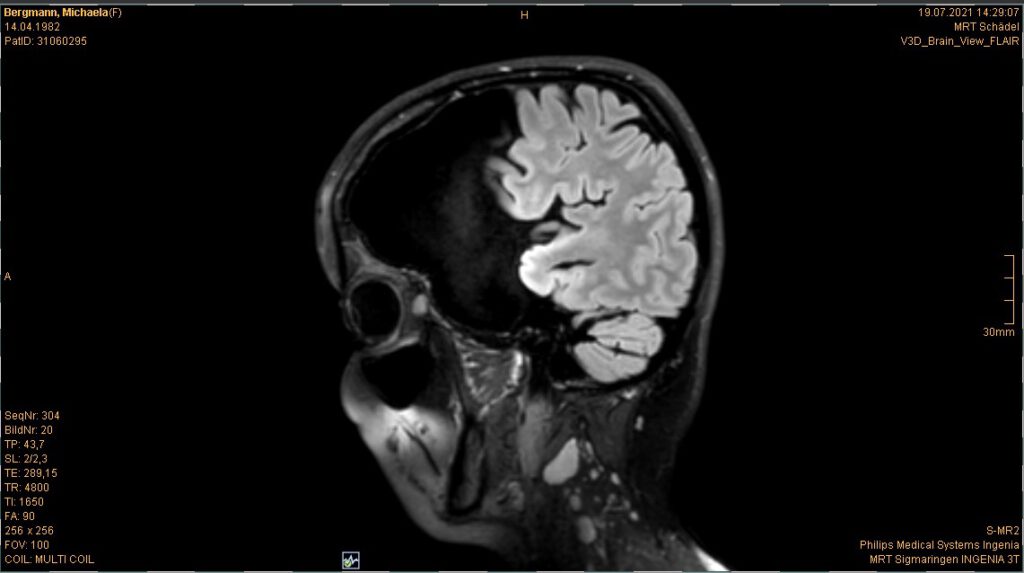

Im Juli stand ja auch noch mein jährliches Kopf MRT an. Ist ja schon quasi „same procedure as every year“. Es gab nichts überraschend Neues oder so. Wenn man es optimistisch sieht kann man sagen: Unverändert. Wenn man es realistisch sieht: gleich beschissen wie vorher

Für alle, die sich neu hier auf meinem Blog tummeln und schon an der ein oder anderen Stelle von meinem „Untermieter“ gelesen haben, sei er hier noch einmal mit den aktuellsten Bildern „vorgestellt“

Die Bilder sind also die aktuellsten vom 19.07.2021. Ja ich weiß, der ist ja riesig, ja ich weiß, dass das ja echt shit ist usw. usw. Aber das weiß ich nun schon seit dreizehn Jahren und ich habe mich damit arrangiert und abgefunden. Womit wir zum nächsten Gedankenthema kommen.

Es ist für mich ja nicht mehr schockierend, wenn ich die Bilder sehen, denn ich weiß ja was mich erwartet. Aber für den ein oder anderen Außenstehenden oder mich noch nicht kennenden Mitarbeiter in der Radiologie im Krankenhaus ist das doch schon immer wieder was Besonderes. Und als ich dieses Mal so den MRT Gang entlang schritt und herein gerufen wurde, wusste die eine Mitarbeiterin, dass ich nun schon zum 37sten Mal das ganze Prozedere über mich ergehen lasse und sagte dementsprechend nicht mehr viel zu mir (bzgl. alles mit Metall muss ausgezogen werden vorher, dann wird der Kopf mit einer Art Kopfkäfig fixiert, dass man ihn während der Aufnahmen nicht bewegt usw.). Es läuft alles wie eine Art Routine und im stillen Einvernehmen zwischen uns ab. Der andere Mitarbeiter der da war, war sichtlich irritiert. Und wollte mir zuvorkommen und mich aufklären, wusste aber auch nicht ob er das, weil seine Kollegin (wohl auch seine Vorgesetzte) schwieg, irgendwie nicht richtig wäre usw. Während ich dann immer so im MRT liege und die Bilder gemacht werden (das dauert dann immer gut so zwanzig Minuten) gehen mir auch meist zig Sachen durch den Kopf. Ehrlich gesagt keinerlei Gedanken bzgl. des MRTs selbst, sondern eher bzgl. dem was seit meinem letzten Besuch hier mal wieder alles so los war und passierte.